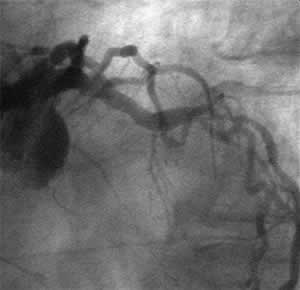

![]() Final |

D-1 : 6 months follow-up angio